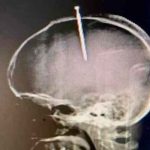

Se incrustó un clavo en la cabeza porque sentía «flojo el cerebro»

Natanael García Polanco, un hombre de 33 años , en República Dominicana resultó con un clavo en la cabeza tras consumir drogas. Según su...